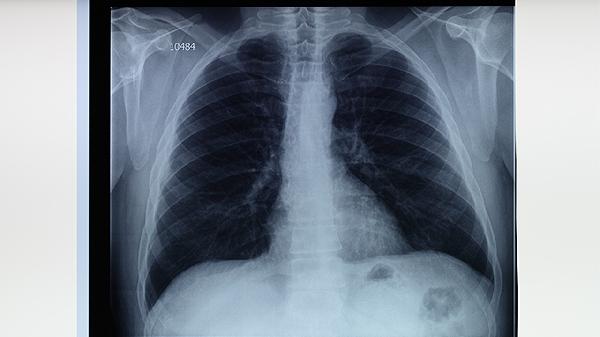

治疗期间每2个月复查痰涂片和培养,影像学检查间隔不超过6个月。治愈后2年内每半年随访,观察是否复发。出现咳嗽加重、咯血等症状需立即复查胸部CT。